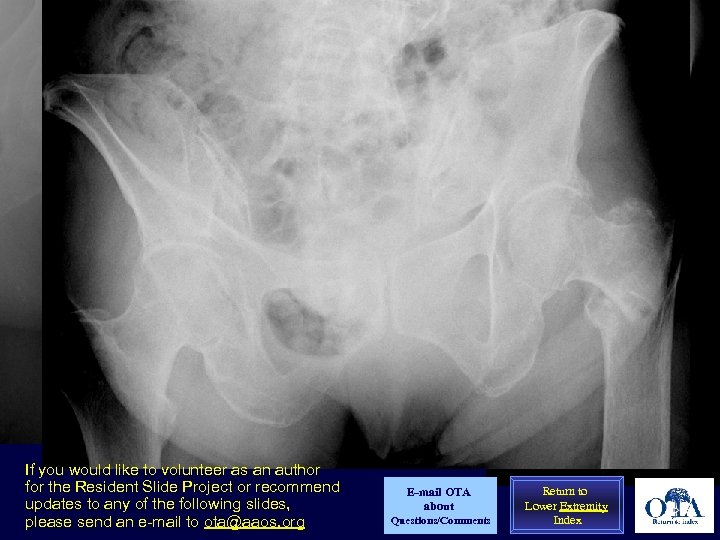

Uncontrolled factor: Bone quality A 33 year old pt with intertrochanteric fracture following a fall from height. Note the dense, cancellous bone throughout the proximal femur; Not at all like a geriatric fracture

Uncontrolled factor: Bone quality 83 yo white woman with unstable intertrochanteric fracture: Note the marked loss of trabeculae